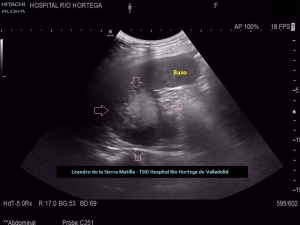

Se realiza estudio de Ecografía Abdominal protocolizado, en el que se observan entre otros hallazgos, varias lesiones esplénicas y ováricas (flechas rosas) junto con una mínima cantidad de líquido libre abdominal.(FIG 1,2 y 3)

1

2

3